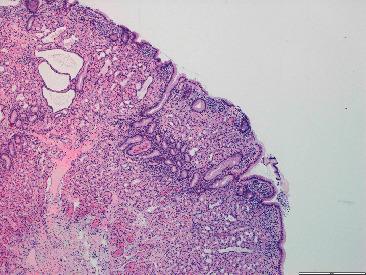

Gardner's syndrome is an autosomal dominant disease caused by a mutation in the gene with 20-30% of cases presenting de novo. This entity is a variant of familial adenomatous polyposis, with a prevalence of 3/100,000 habitants. It may present as early as 2 months of age with a variety of both colonic and extracolonic symptoms. We report a case of a 21-year-old man, without any known family history, presenting with microcytic hypochromic anemia and constitutional symptoms for two months. Ultimately, after the etiological study, Gardner syndrome diagnosis was established as an index primary familiar case. Gardner syndrome is a clinical challenge which requires a prompt suspicion in order to reach its diagnosis. Given the malignant evolution of adenomas in 100% of untreated patients, early identification of extraintestinal manifestations (identifiable prior to colonic symptoms) is of the essence. A consequent endoscopic study to confirm gastrointestinal involvement is essential for a more favorable prognosis.

加德纳综合征是一种常染色体显性疾病,由该基因的突变引起,20%至30%的病例为新发。该病症是家族性腺瘤性息肉病的一种变体,发病率为十万分之三。它最早可在2个月大时出现,伴有多种结肠和结肠外症状。我们报告一例21岁男性病例,无任何已知家族病史,出现小细胞低色素性贫血和全身症状达两个月。最终,经过病因学研究,加德纳综合征被诊断为原发性家族性病例。加德纳综合征是一项临床挑战,需要迅速怀疑以便做出诊断。鉴于100%未经治疗的患者腺瘤会发生恶性演变,早期识别肠外表现(在结肠症状出现之前即可识别)至关重要。因此,进行内镜检查以确认胃肠道受累对于获得更良好的预后至关重要。